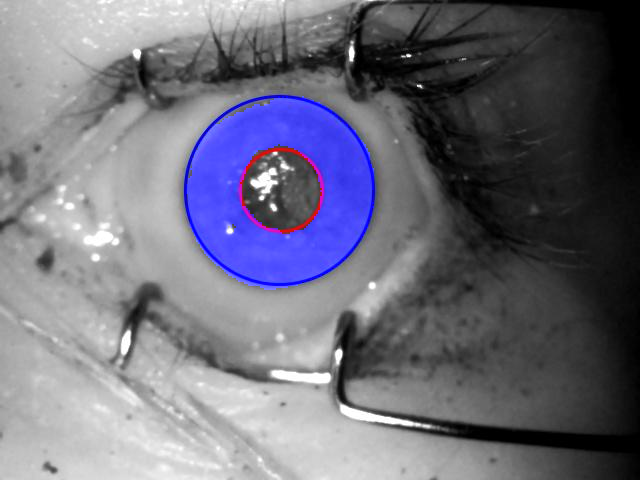

In addition to the model described above, in this work we have implemented and trained two additional models, ending up with three models in total, which are detailed below and their example predictions given in Fig. 2

OSIRIS segmentation, normalized images, and normalized masks

coarse CNN binary predictions with fitted Hough circles, segmented images, normalized images, and normalized masks

fine and fine v2highres CNN segmented images, normalized images, and normalized masks

4.3 Iris and mask normalization

For the proposed method to serve as a drop-in replacement for the Daugman method recognition pipeline, the prediction obtained from the DCNN-based segmentation has to be correctly normalized onto a dimensionless polar-coordinate rectangle. For this stage, a method for localizing pupillary and limbic iris boundaries has been devised, which employs a Hough transform that is applied to the prediction obtained from the coarse segmentation model, similarly to the methodology introduced in [21] and [22], as this model yields the smoothest prediction. These boundary parameters are then used in all subsequent experiments, including those involving the fine and fine v2highres models. The segmentation methodology employing the coarse segmentation model is visualized in Fig. 2. Similar results are then presented in Fig. 3 for the two remaining fine-grained models. Notably, the original fine model from [10] seems to over-aggressively mask out some portions of the iris, while at the same time mistakenly denoting some portions of the pupil as iris. This is fixed in the fine v2highres model, which was trained with twice the iterations count, cf. right side of Fig. 3.